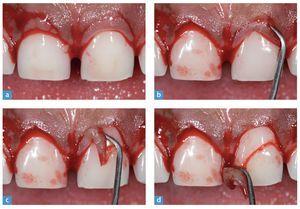

Se alargaron quirúrgicamente las coronas de los seis dientes anteriores superiores. A partir de un sondeo del surco se determinó la longitud definitiva de las coronas mientras el paciente estaba anestesiado. Se establecieron dos puntos: el límite amelocementario (collum dentis) y la altura de la cresta ósea. El biotipo periodontal fue clasificado como grueso y plano. Tras la operación, el nuevo recorrido del límite gingival debía situarse 3 mm por encima del borde óseo del hueso alveolar (fig. 6).

Fig. 6. Tomas de detalle de la gingivectomía, mostrada en los incisivos centrales superiores. a La delimitación del nuevo recorrido gingival, determinada por el sondeo del tejido blando. b a d Se elimina el tejido sobrante mediante una cureta afilada.

Un corte falciforme, basado en sondeos del hueso y de las partes blandas, expone la superficie dental deseada. Tras la retirada del tejido blando se abrió un único colgajo y se remodeló la estructura ósea a fin de obtener una nueva anchura biológica (fig. 7). Las figuras 8a y 8b muestran el estado del tejido blando suprimido al principio de la gingivectomía en comparación con la situación poco antes del alargamiento de las coronas.

Fig. 7. a Se abre hacia apical un colgajo gingival para acceder al hueso maxilar. Obsérvese el grosor del hueso, típico del tejido blando periodontal grueso. b Una comparación entre la sustancia ósea del incisivo central derecho, en el que ya se había remodelado el hueso, y el hueso intacto del incisivo central izquierdo. c La delimitación de la nueva forma ósea para el incisivo central izquierdo. d El recorrido de la nueva forma ósea.

Fig. 8. a La delimitación inicial de la gingivectomía, como estaba previsto, 1 mm por debajo del límite amelocementario. b El recorrido gingival tras la sutura.